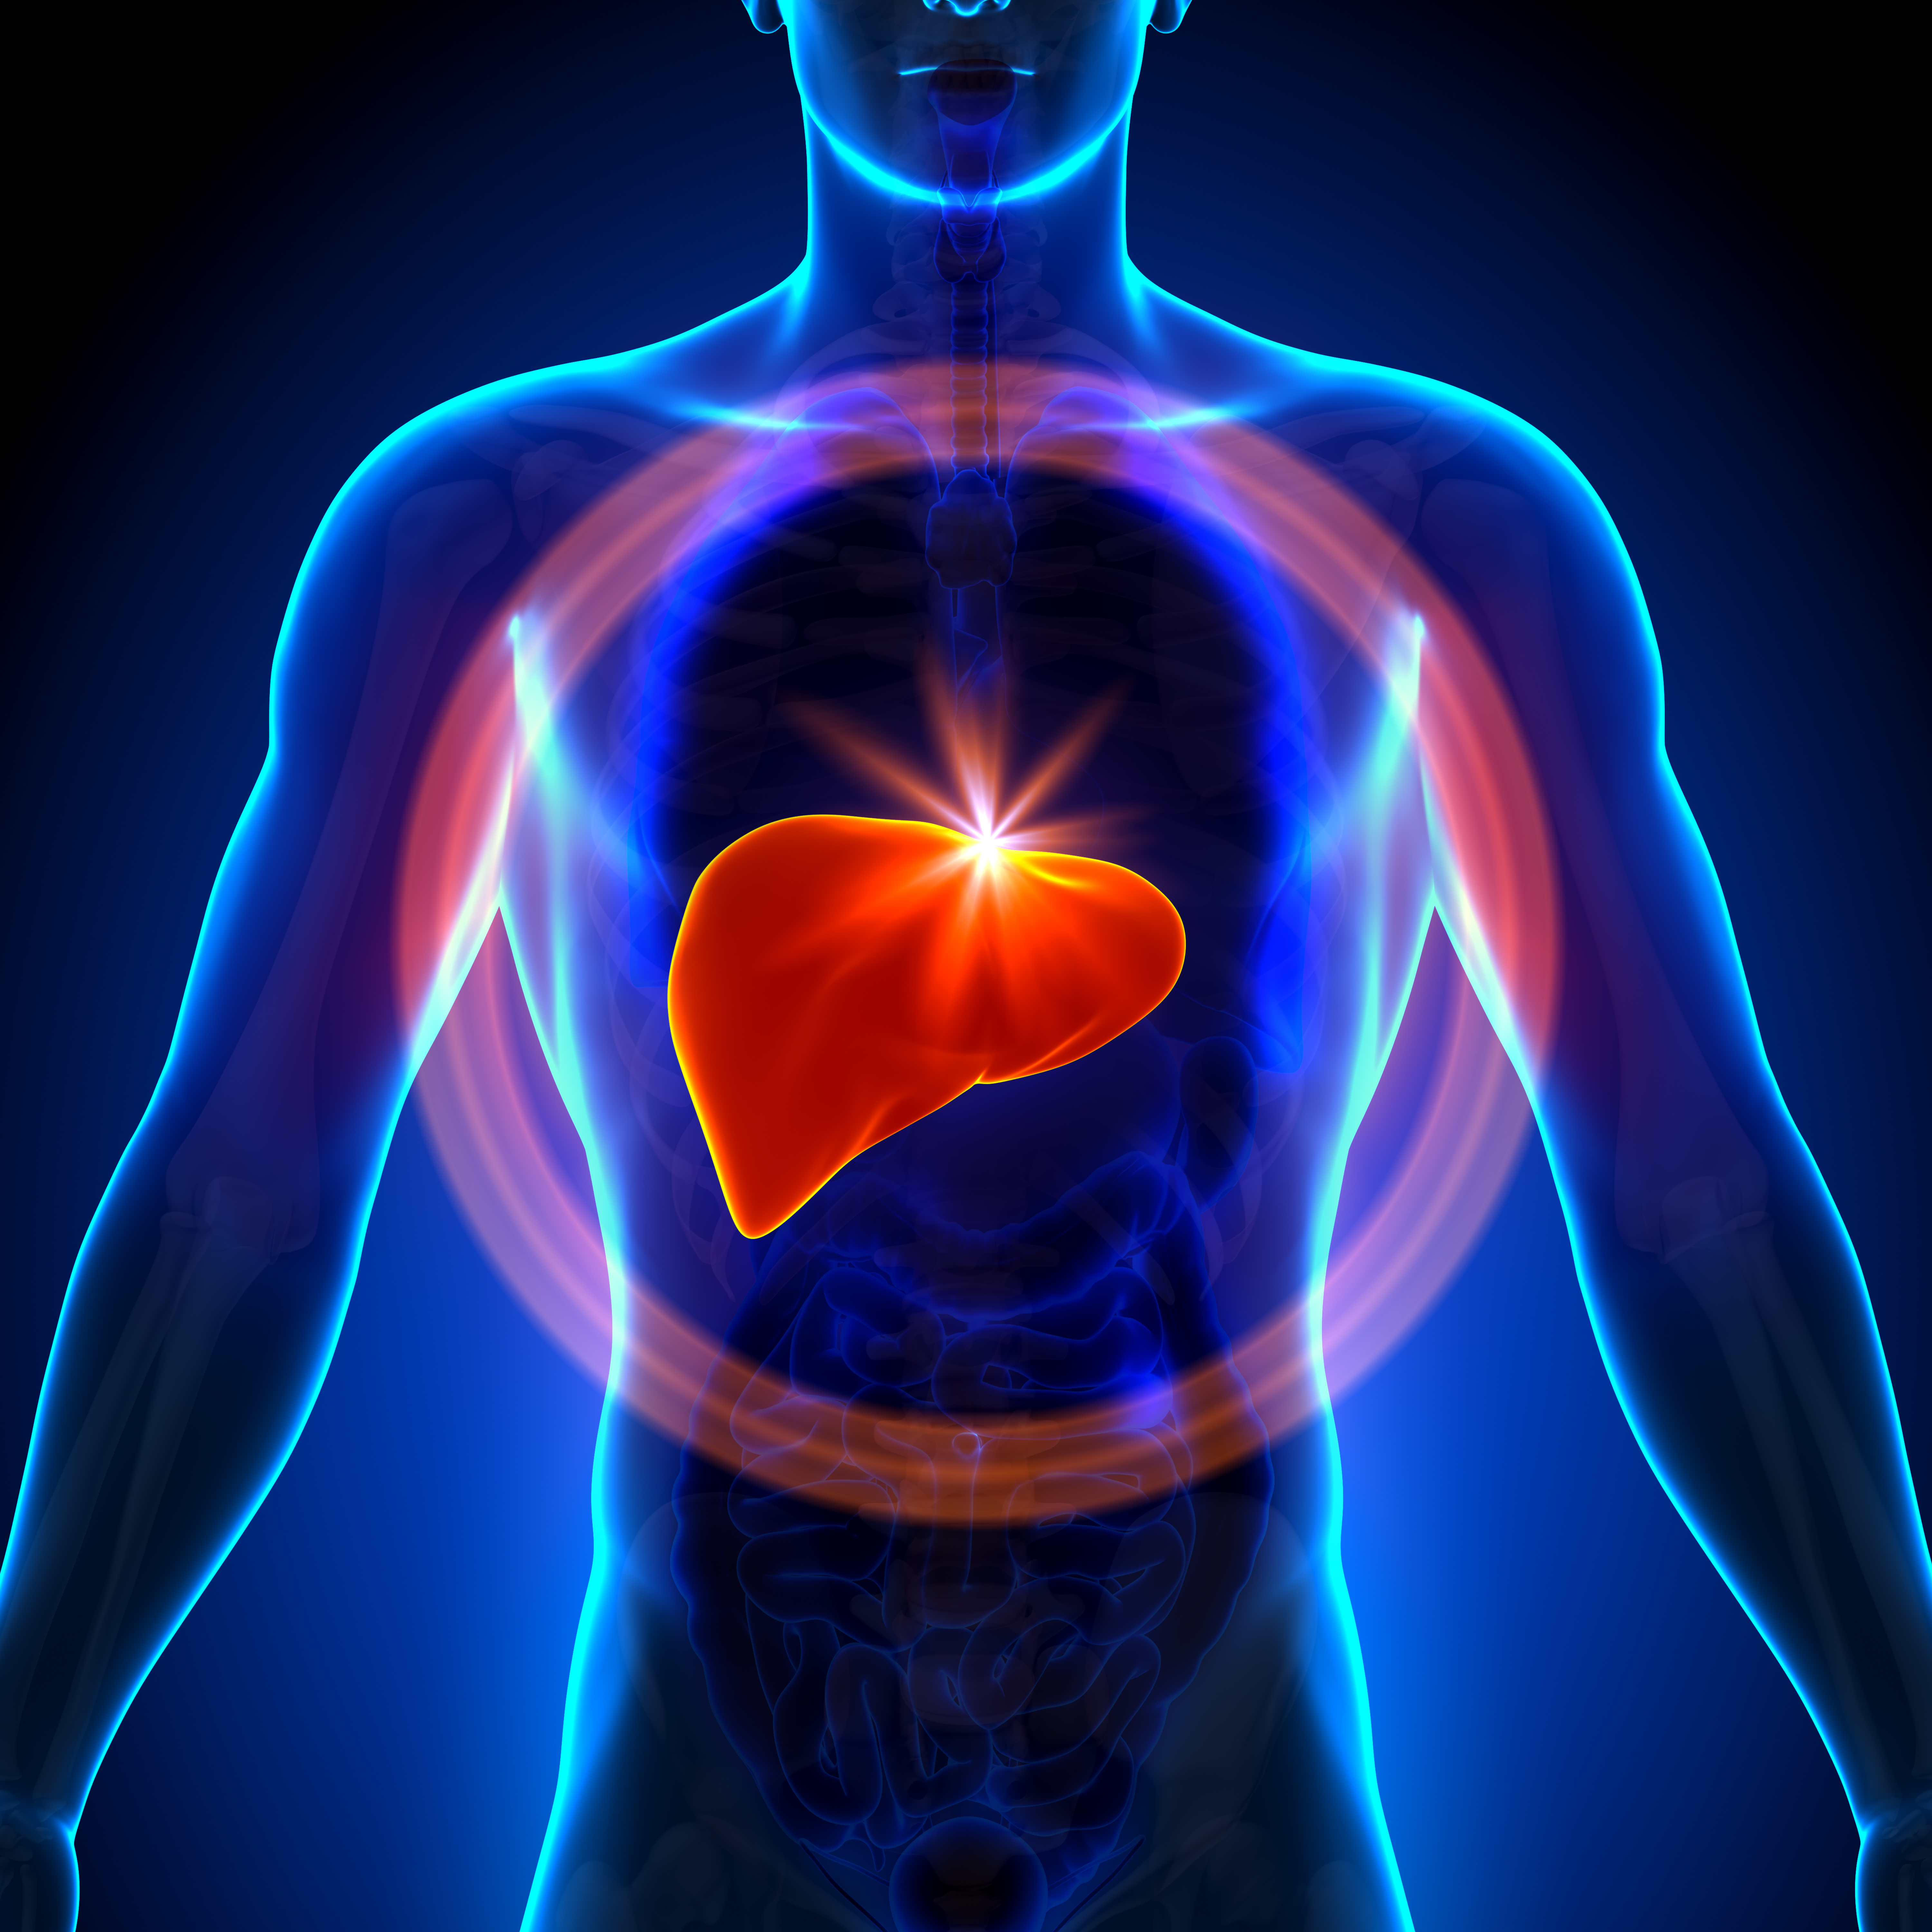

В последние годы в социальных сетях и блогах все чаще встречается необычное явление, известное как “Печень фото”. Этот термин относится к художественному стилю, при котором фотографии печени человека становятся объектом эстетического восприятия и даже искусства. Такие изображения, часто с высоким разрешением и детальной проработкой текстур, привлекают внимание не только медиков и исследователей, но и широкой публики, вызывая удивление и восхищение своей красотой и уникальностью.

Печень фото